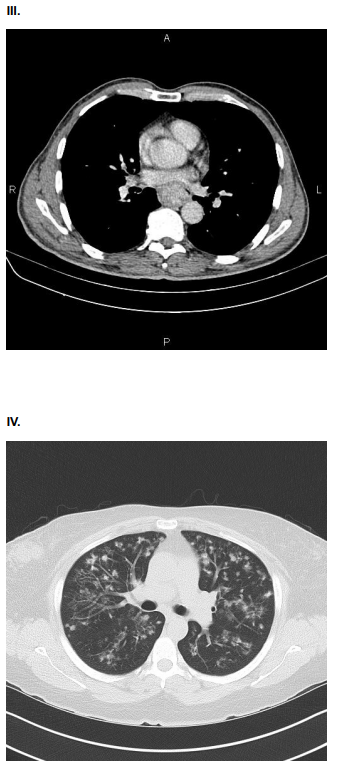

AMV, 75 anos, tabagista, com queixa de dor torácica

súbito, do tipo lancinante. Ao exame físico: Regular estado

geral. ACV: RCR em 2T, pulsos radiais assimétricos. PA:

150x80 mmHg. FC 110. Sat O2 90%. Solicitado ECG e

Tomografia de Tórax e Abdome com contraste.

Assinale a alternativa que contenha o achado compatível com o quadro clínico da paciente.